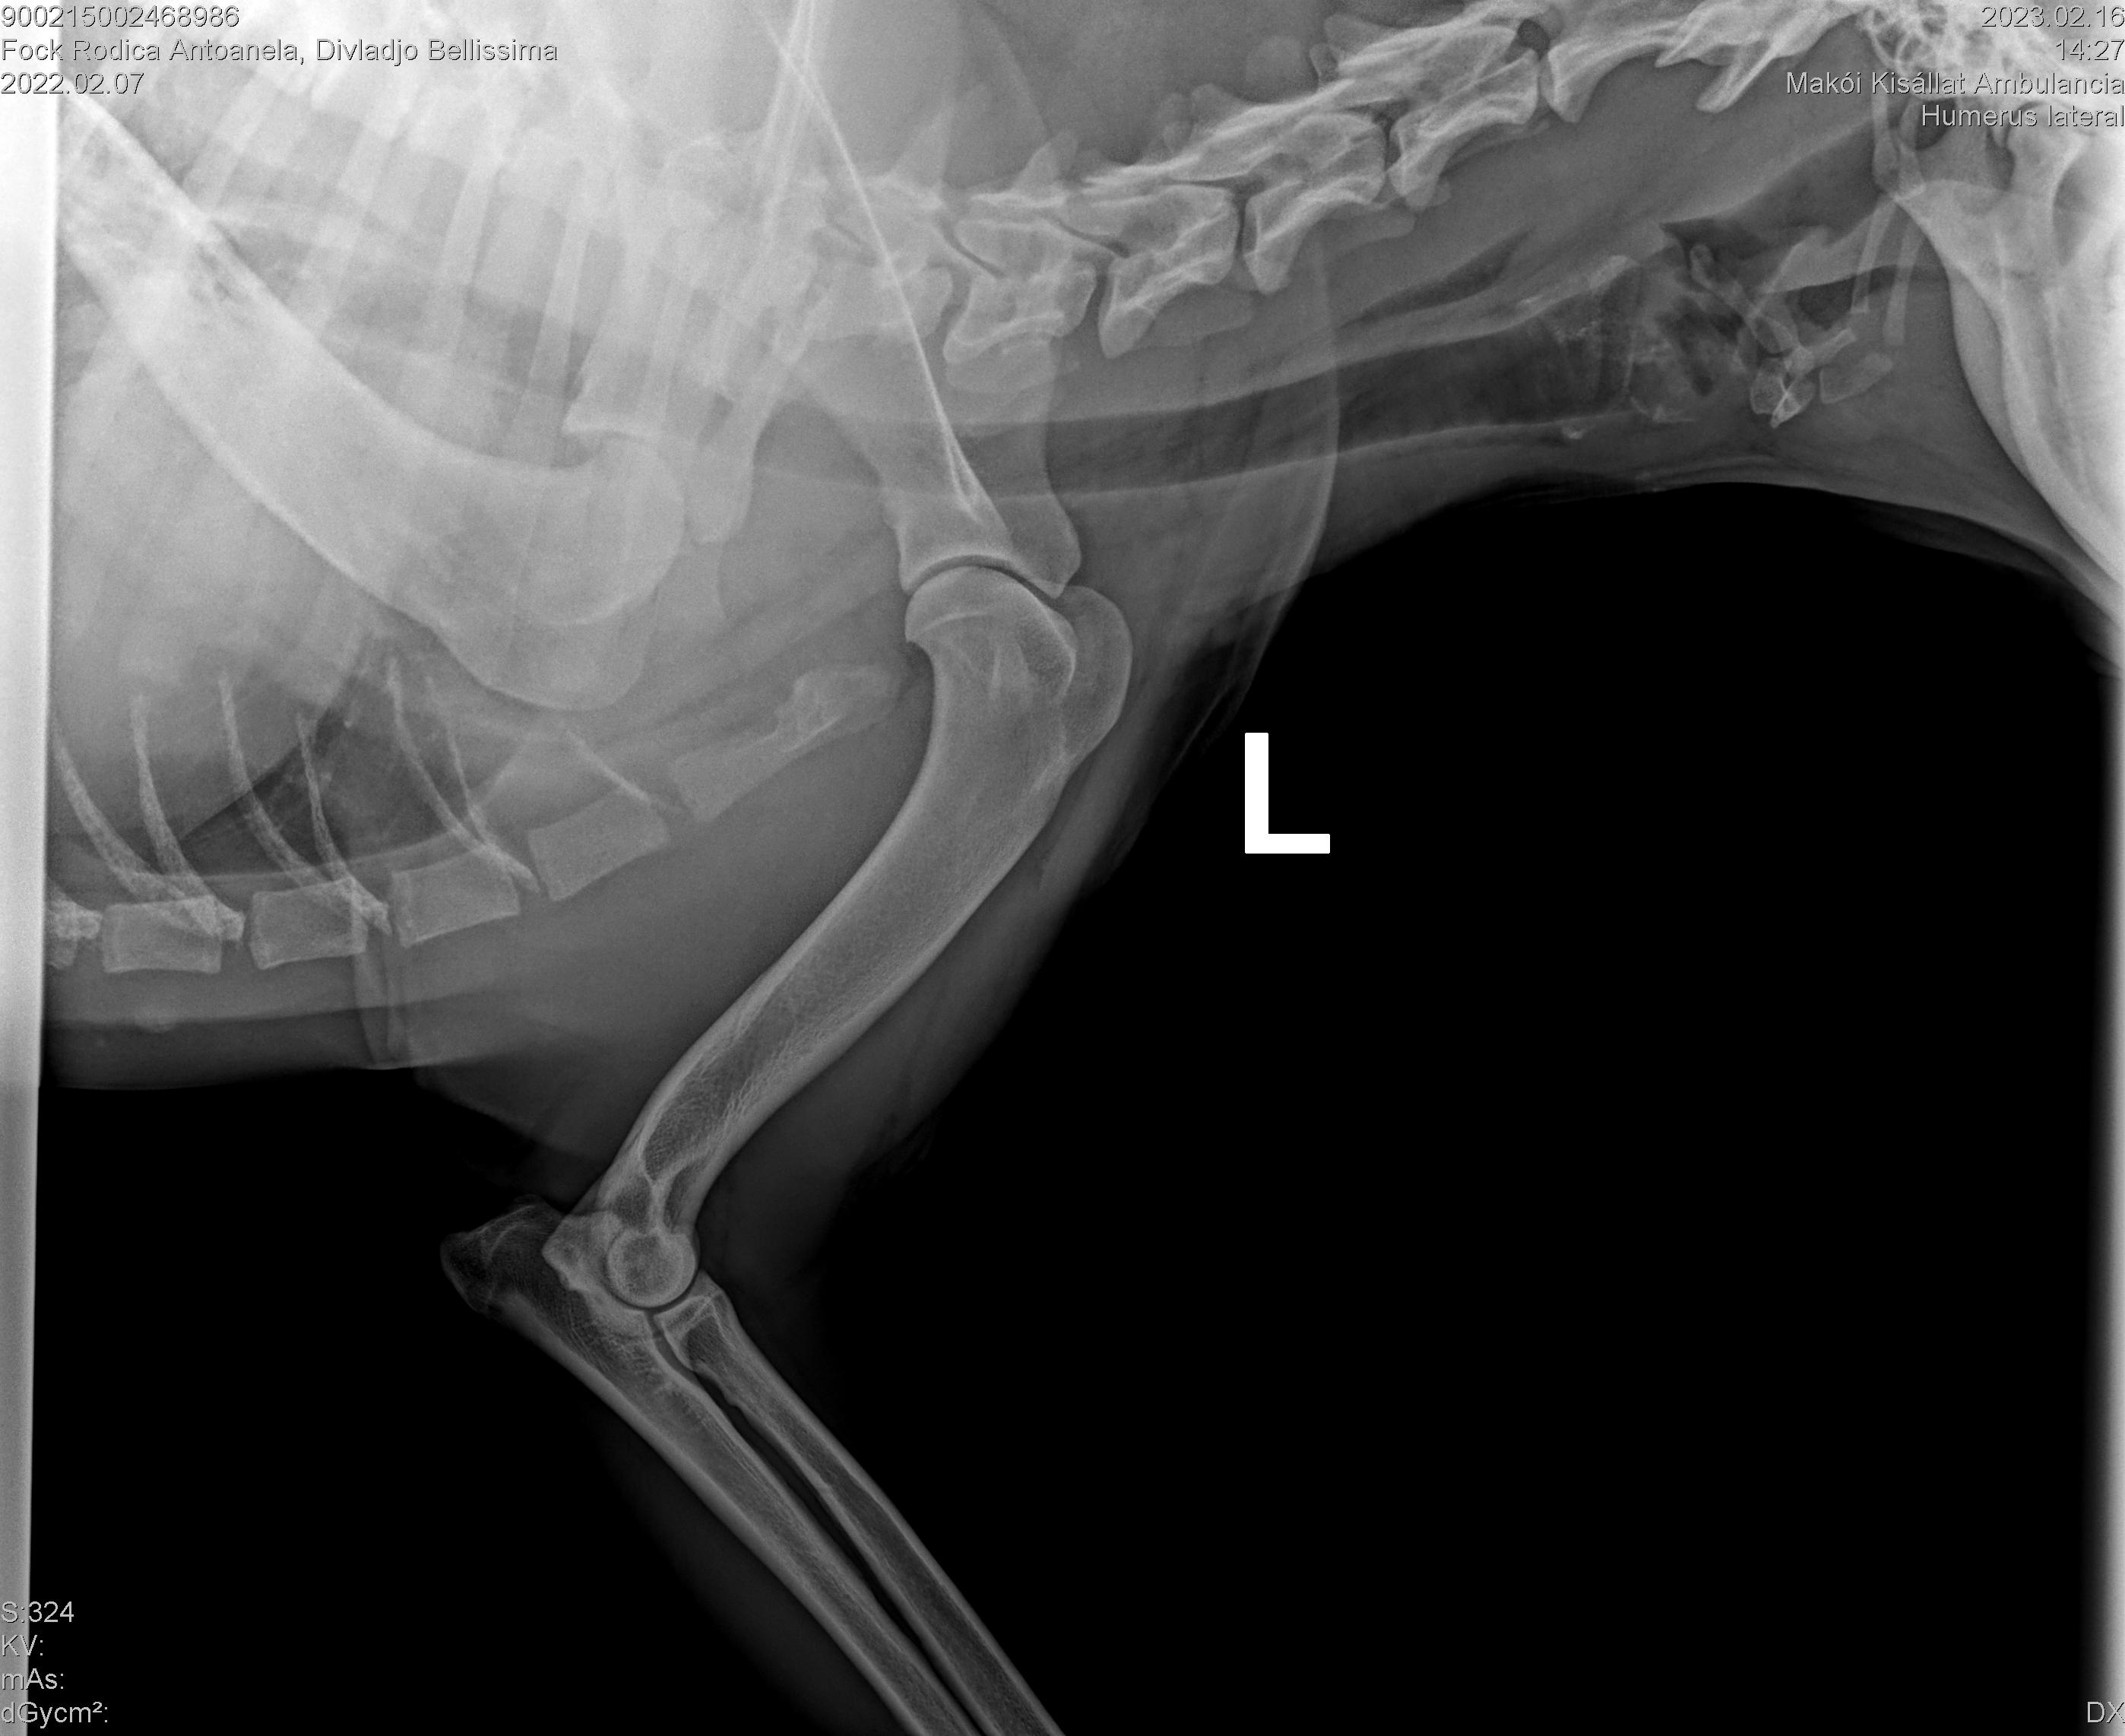

DIVLADJO BELLISSIMA

( BELLISSIMA )

Data nasterii:

07.02.2022